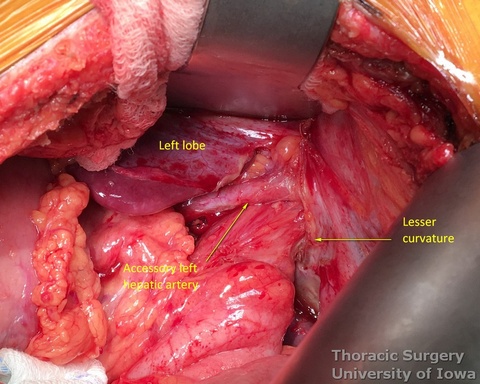

- The replaced/accessory left hepatic artery, if present, can be divided.

- Once the stomach is mobilized and reflected anteriorly, the left gastric vascular pedicle is identified and dissected close to the origin for adequate lymphadenectomy. Care is taken to not injure splenic artery and pancreas.